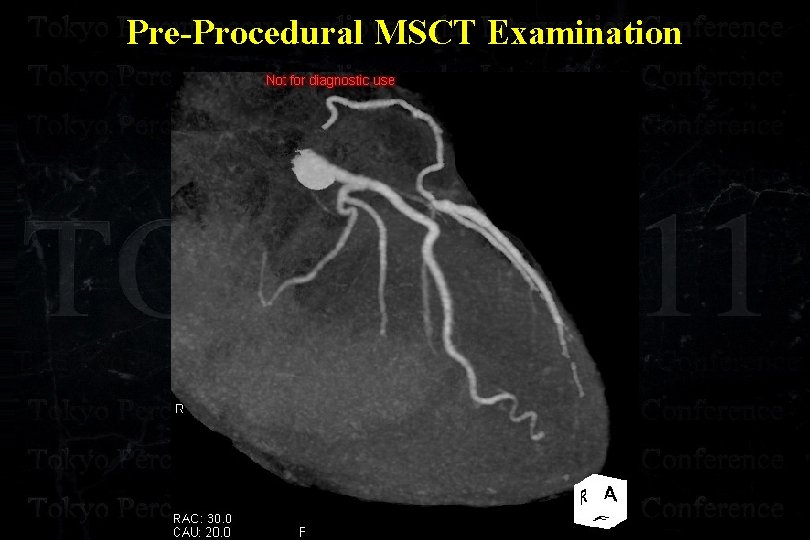

Pre-Procedural MSCT Examination